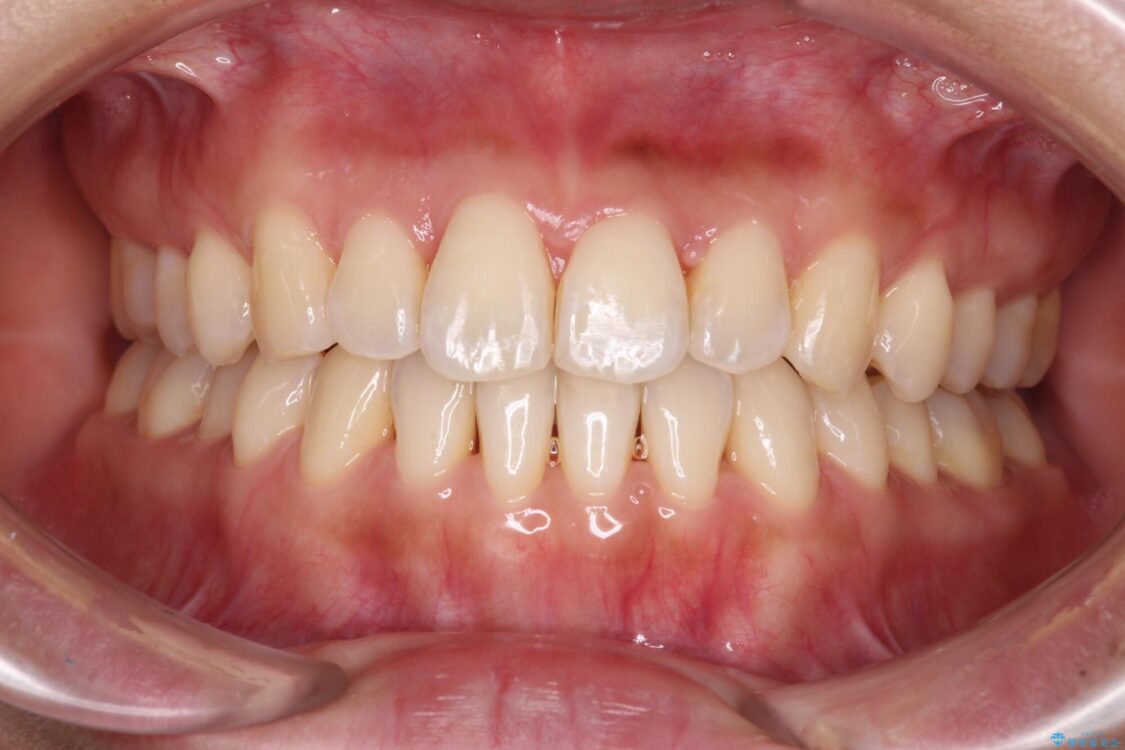

装着時間を守ってくださったので、予定通りの期間で終えることができました。インビザライン特有の、奥歯の咬み合わせの問題もなく、しっかりと歯列を改善することができました。

治療後

• 【モニター】前歯のデコボコをインビザラインで改善 治療後画像